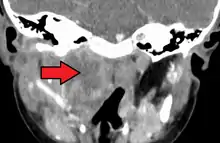

| A lateral cervical spine x-ray demonstrating prevertebral soft tissue swelling (marked by the arrow) as seen in a person with a retropharyngeal abscess. | |

X-ray of the neck often (80% of the time) shows swelling of the retropharyngeal space in affected individuals. If the retropharyngeal space is more than half of the size of the C2 vertebra, it may indicate retropharyngeal abscess.[5]